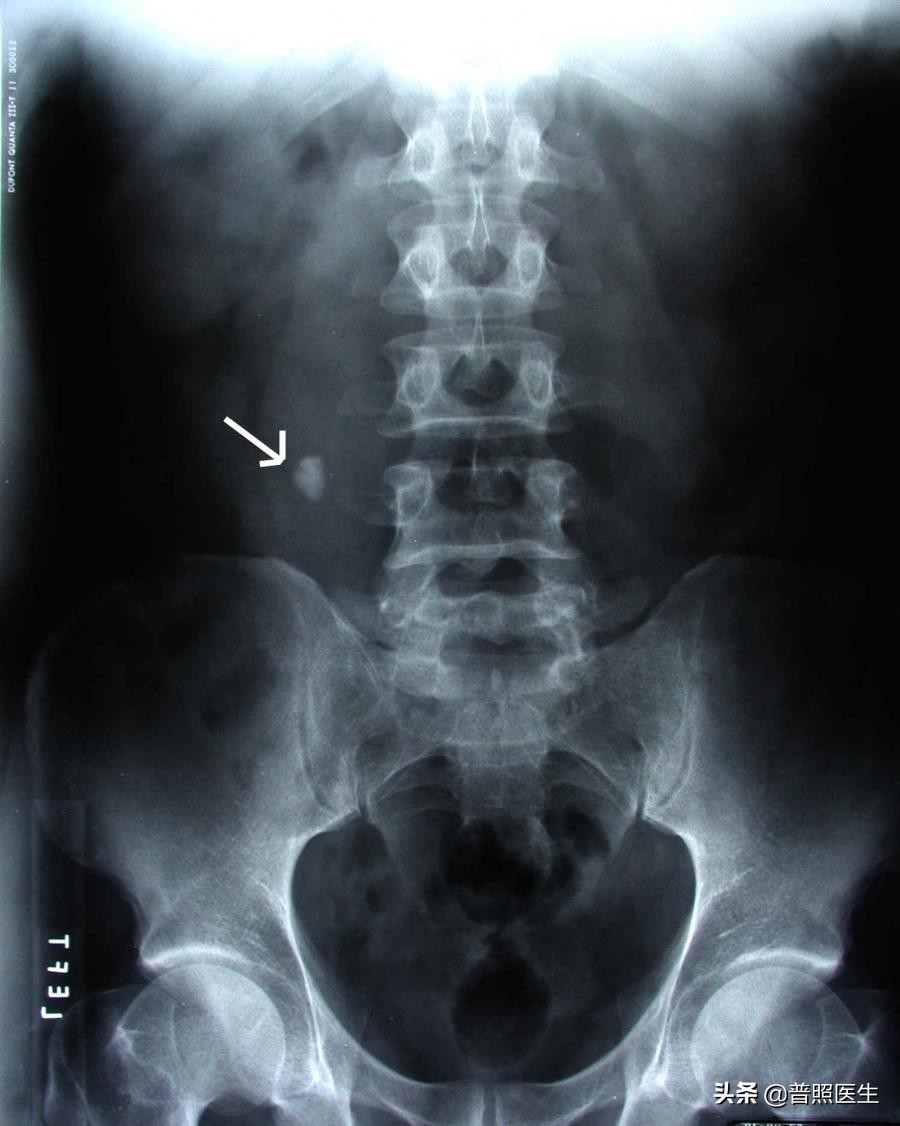

KUB腹部X线平片:也很便宜,100来块就可以了,再对比我们上面说的结石分类,就可以找出草酸盐结石和磷酸盐结石的位置。但是孕妇不能照。